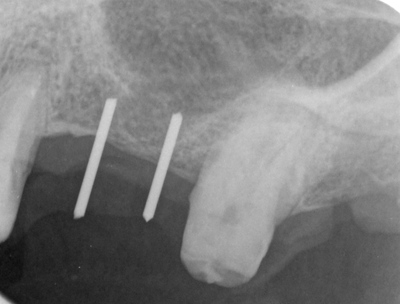

HOME > ブログ 一覧 > 左上56部へのサイナスリフトを伴うインプラント治療 2020.01.28左上56部へのサイナスリフトを伴うインプラント治療 左上56部2本欠損部へのインプラント。 術前写真。 術前CT。 インプラント治療行うには全く骨が不足している。 ラテラル法によるサイナスリフトを行い、インプラントを同時埋入。 使用インプラントはアストラEV。 間隔が狭いため、細めのインプラント2本で対応した。 術後。 骨が移植されているのが分かる。 複雑、難症例は当院の得意とするところです。 Recent Entries アライナー矯正(インビザライン、シュアスマイル)費用を2023年 1月から改訂させていただきます(01/09) 本年もよろしくお願いいたします(01/02) 年始の診療について(01/01) 新しいWEBへ移行、年末年始の診療のお知らせ(12/29) ダラダラ根管治療行っても治らないという事(12/21) Category その他の治療(126) インビザライン・矯正(52) インプラント治療(216) ホワイトニング(47) メインテナンス(21) 包括診療(95) 医院からのお知らせ(249) 審美治療(128) 日々雑感(283) 根管治療(100) 歯周病治療(90) 矯正(73) 補綴治療(45) 補綴治療カテゴリを追加(1) 診療全般(44) Archive 2023年1月(3) 2022年12月(6) 2022年11月(14) 2022年10月(6) 2022年9月(8) 2022年8月(7) 2022年7月(13) 2022年6月(8) 2022年5月(7) 2022年4月(7) 2022年3月(6) 2022年2月(7)